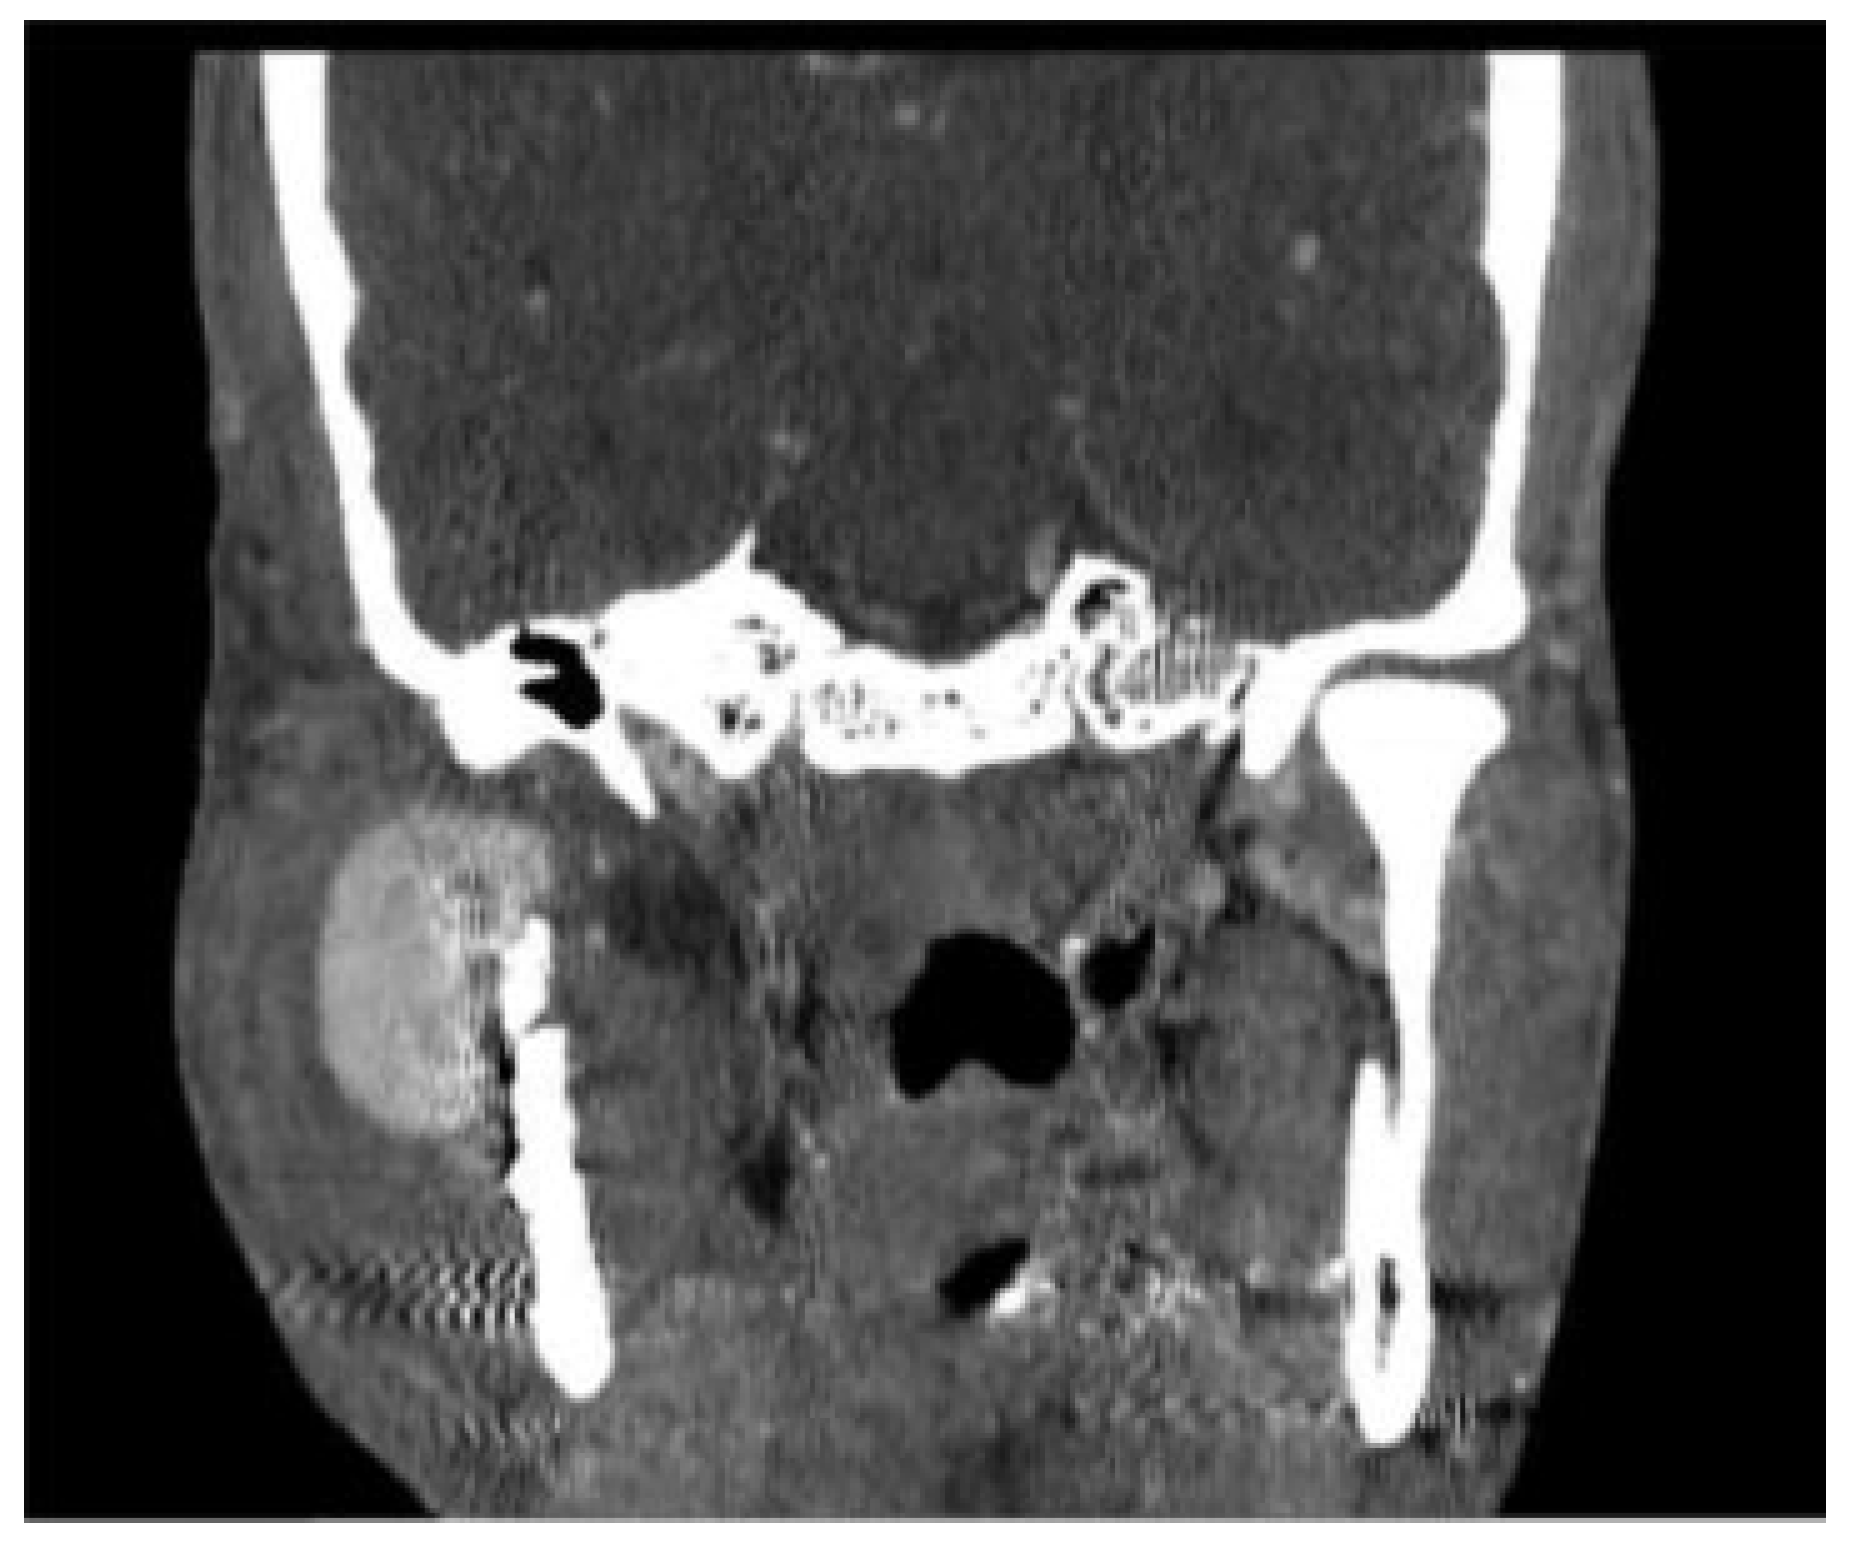

Pseudoaneurysm following Endoscopic-Assisted Repair of Subcondylar Fracture

:Presentation of Case